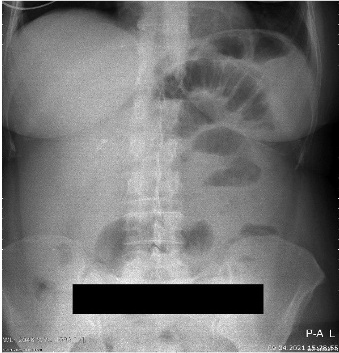

A 46-years-old female patient presented to the emergency department with clinical signs of intestinal obstruction. The patient reported cramp and abdominal pain, and absence of flatus and stool passage one day prior to the exam. She had no previous abdominal surgery nor visible groin herniation on physical examination. The serum analysis showed C-reactive protein value of 5.80 (0.0–5.0 mg/L) and serum Iron level of 5.80 (6.6–28.3 μmol/L). Plain abdominal upright X-ray image confirmed the suspicion for intestinal obstruction (Figure 1).